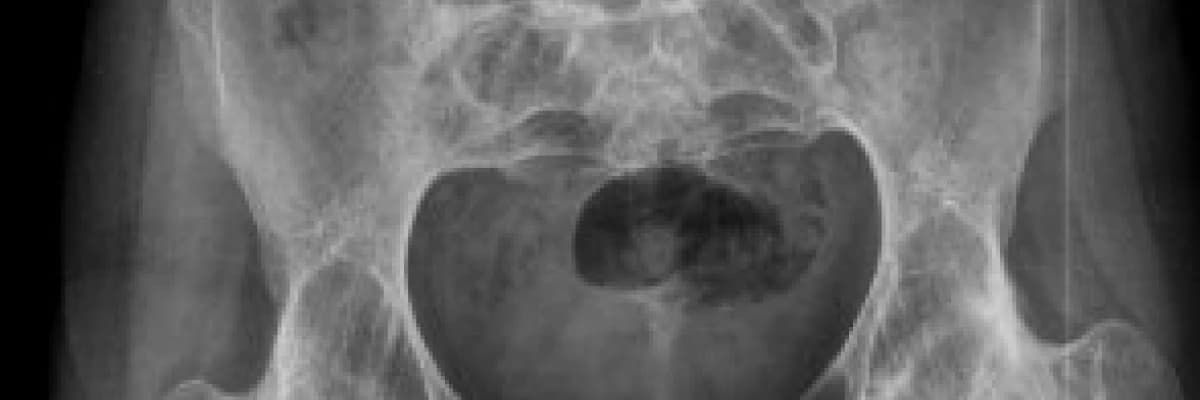

Uzun süreden beri devam eden bel ağrıları, sabahları yataktan sanki donmuşçasına kalkma, zaman zaman kalçalarına giren şiddetli ağrılar ve onlarca tetkik tahlil derken bir gün bu teşhis konulmuştu sonunda.... Namı değer AS, yani kamburluk hastalığı. İşte o andan itibaren eşe, dosta, internete ve dahi kimi görse hastalığını bir şekilde anlatarak kamburluktan kurtulmanın yolunu aramaya başladı...

AS aslında standart bir hastalık değildir. Yani her teşhis koyduğumuz kişi kendisini hemen rahmetli Suna Pekuysal ve Ahmet Mete Işıkara ile özdeşleştiriverir. Ancak bu davranış aslında kocaman bir yanlıştır. Her hastamızın ayrı bir seyri vardır ve hastalık kişiye göre ciddi farklılıklar gösterir. Kimin kötü gideceğini Romatoloji uzmanı bilir aslında ve tedaviyi de buna göre ayarlar. Bu yazının konusu da, hastalarımızın nasıl yaşamaları gerektiğidir. Biz bu önerileri verirken, tıbbi referanslara dayalı bir liste hazırladık sizlere.